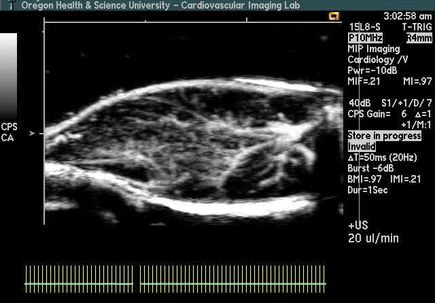

VIDEO: Microbubble treatment, after therapy

Ultrasound of blood flow after microbubble treatments. (OHSU)

VIDEO: Microbubble treatment, before therapy

Ultrasound of blood flow after microbubble treatments. (OHSU)